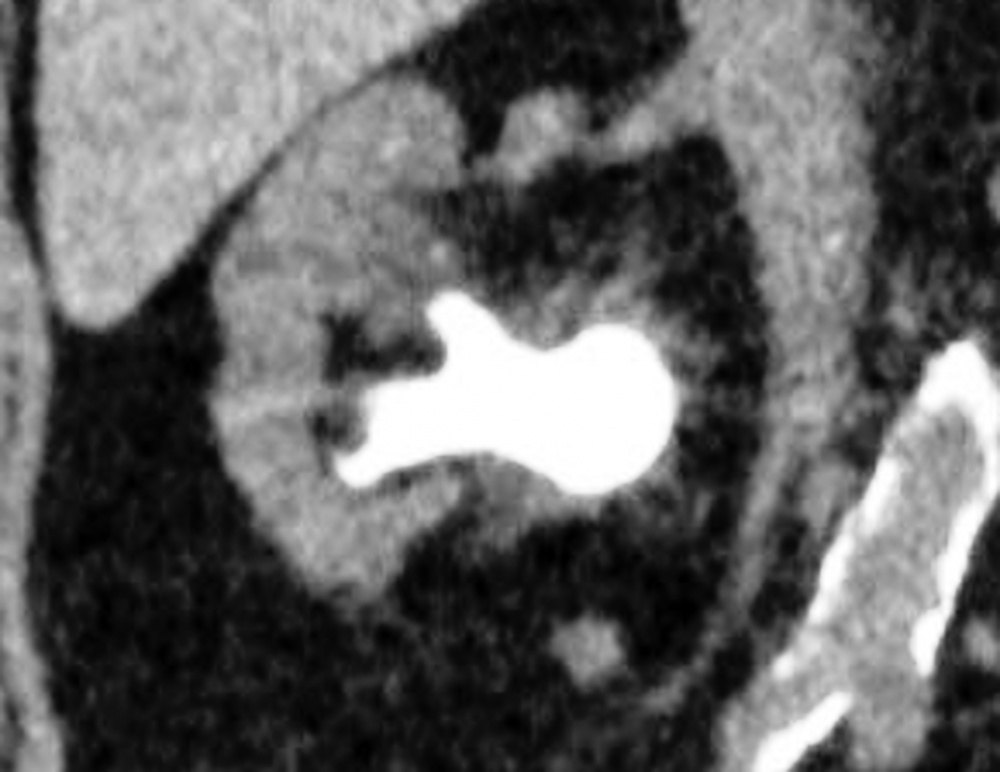

Ergibt sich in der Zusammenschau der Diagnostik der Verdacht auf eine Harnsteinerkrankung, sollte eine Niedrig-Dosis-CT des Abdomens zur genauen Lokalisation des Konkrements und zur weiteren Therapieplanung erfolgen. Hierbei kann die Bestimmung der Hounsfield-Einheiten[1] Hinweise auf die Steinzusammensetzung geben.

Bei der PCNL handelt es sich um ein endoskopisches Verfahren, wobei der Zugang durch eine direkte Punktion der Niere durch die Haut erfolgt. Die Punktion wird durch Ultraschall und Röntgen gesteuert (Abbildung 8). Die Wahl der Punktionsstelle erfolgt nach dem Prinzip der besten Erreichbarkeit [16]. Im Allgemeinen wird hierbei die untere Kelchgruppe punktiert, da dort das Risiko einer Verletzung benachbarter Organe sowie auch der Stein-Haut-Abstand gering ist [6]. Durch ein Endoskop kann nach erfolgreicher Punktion die sofortige Bergung bzw. die Desintegration des Harnsteins erfolgen. Die Fragmente werden je nach Technik ausgespült (z. B. Mini-PCNL mit offenem Spülsystem), mit Körbchen geborgen oder gehen auf natürlichem Weg ab. In den meisten Fällen wird intraoperativ eine perkutane Nephrostomie oder ein DJ eingelegt, um den Harnabfluss zu gewährleisten [16, 6].